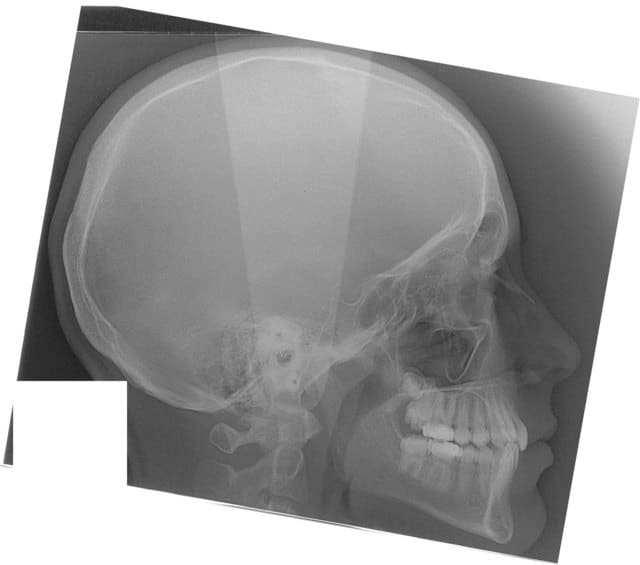

22/05/2008 à 00h10

début 2008,quadhélix en 0.28,pour vestibuler la 2,ce qui est fait

Tele2002 qhiepn - Eugenol

Tele2007 b6yul0 - Eugenol

et les profils

Profil2002 rznvai - Eugenol

Profil2007 dxpeqm - Eugenol